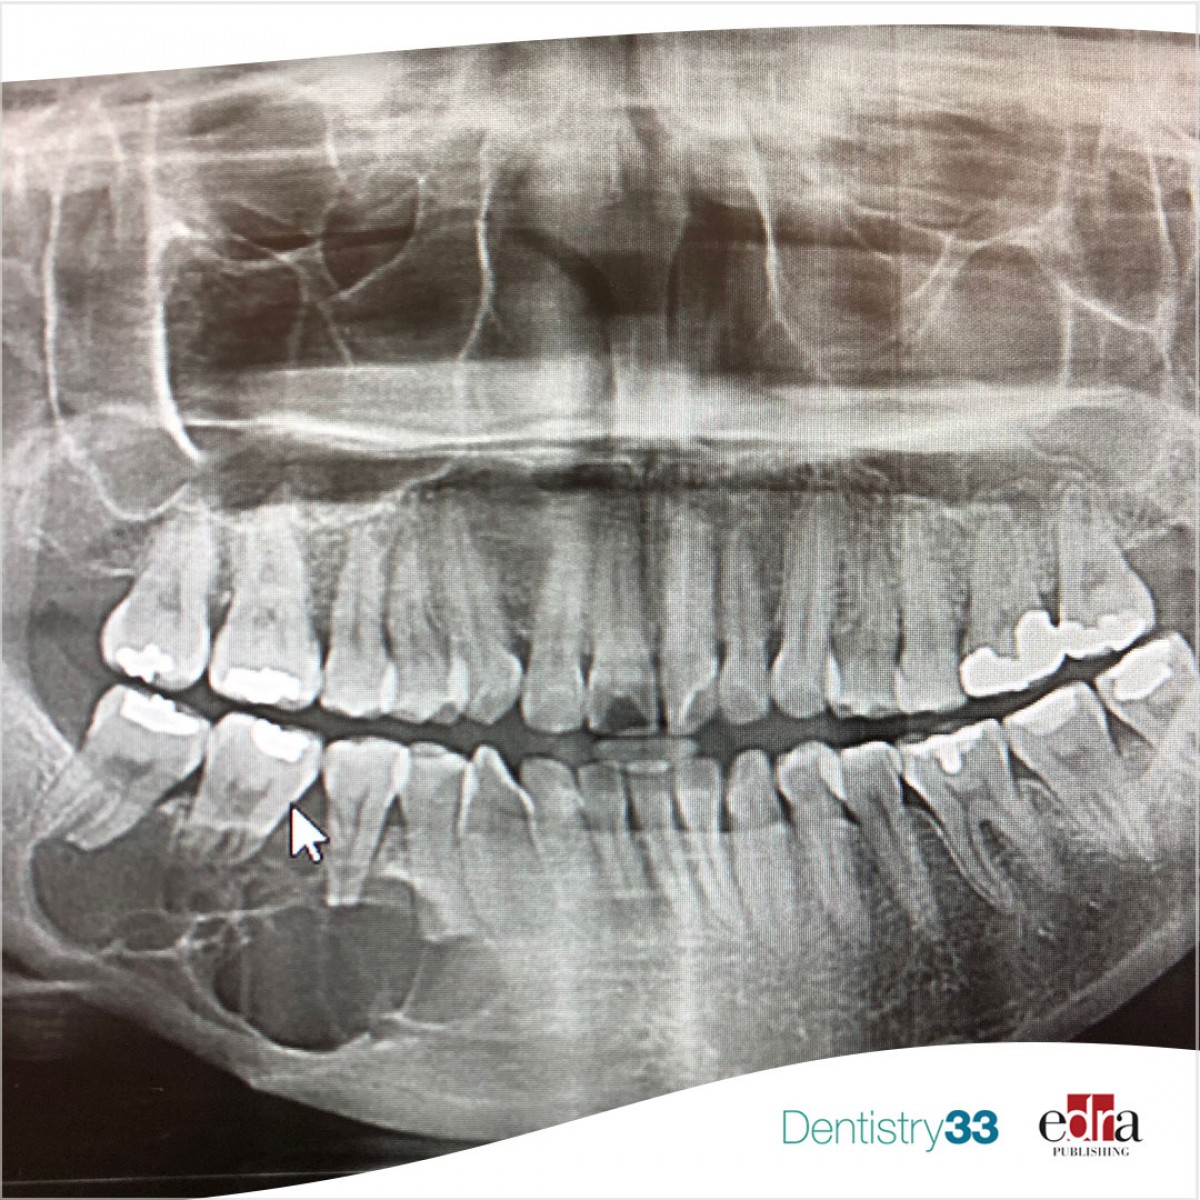

Inflammation of this membrane can be caused by several factors, including respiratory tract infections, inhalation of irritants and infectious processes extending to the maxillary sinuses. The maxillary sinuses may extend towards the alveolar process of the maxillary bones, showing a very close anatomical relationship with the apices of the maxillary teeth, especially molars and second premolars. Several literature studies have reported that the evolution of an odontogenic dental infection can lead to inflammatory changes in the Schneiderian membrane, even without its perforation. Therefore, the pathological effects of odontogenic infections could naturally be considered as etiological factors of sinusitis.

Researchers included 38 studies in the qualitative analysis and 31 in the meta-analysis. Only 12 studies (31.6%) met all elements of the methodological quality checklist. Overall, the studies reported measures of prevalence per maxillary sinus or patient. The pooled prevalence of MSOO was found to be 51% per maxillary sinus. Apical lesions, periodontitis, moderate and severe bone loss were significantly associated with MSOO. However, the certainty of the evidence for associations was very low.

From the data of this study, the researchers concluded that the pooled prevalence of MSOO at CT evaluation is 51% per maxillary sinus and 50% per patient. Therefore, half of maxillary sinusitis can be of odontogenic origin. Apical lesions, periodontitis and moderate and severe bone loss are significantly associated with MSOO.